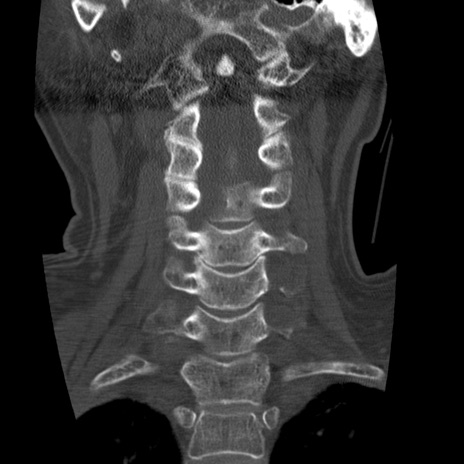

症例50 頚椎CT(冠状断像)

【症例】60歳代女性

【主訴】後頭部〜右後頸部にかけての痛み

【現病歴】本日飲食店でコーヒーを飲んでいたところ、突然後頭部〜右後頸部にかけて痛みが出現し、右上肢の感覚障害を伴ったため救急要請。

【身体所見】脳神経学的に明らかな異常所見を認めず。右上肢に軽度の感覚障害あり。

異常所見と診断は?

頚椎CT